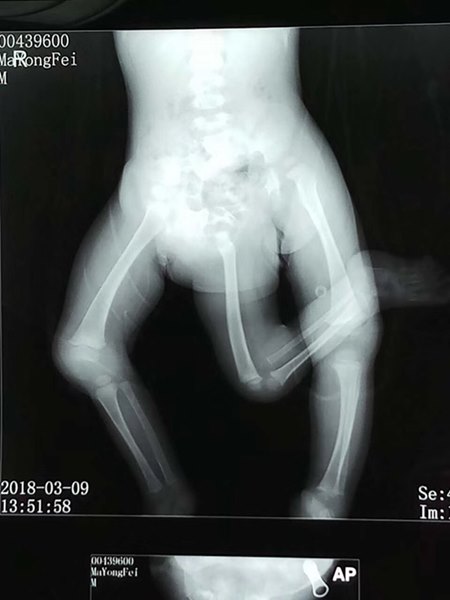

วันที่ 20 มีนาคม 2561 เว็บไซต์เซี่ยงไฮ้อิสต์ รายงานว่า แพทย์ในโรงพยาบาลที่เซี่ยงไฮ้ ประเทศจีน ได้ดำเนินการผ่าตัดที่ซับซ้อนเพื่อช่วยเหลือเด็กชายวัย 11 เดือน ผู้เกิดมาพร้อมกับความผิดปกติตั้งแต่อยู่ในครรภ์มารดา ซึ่งทำให้เขามีขางอกออกมาถึง 3 ข้าง

นอกจากนี้เสี่ยวเฟยยังมีปัญหาที่เท้าขวาของเขาซึ่งมีลักษณะผิดรูป ดูคล้ายกับมือมากกว่าเท้า ทำให้มันไม่สามารถใช้งานได้อย่างเหมาะสม ดังนั้นนอกจากแพทย์จะต้องทำการผ่าตัดนำขาข้างที่ 3 ของเขาออกแล้ว ยังจะต้องตัดเท้าขวาของเด็กชายทิ้งไป แล้วนำเท้าที่มีลักษณะสมบูรณ์จากขาข้างที่ 3 นี้ เข้าไปต่อให้แทน

นั่นทำให้การผ่าตัดช่วยเหลือเด็กชายกลายมาเป็นการผ่าตัดที่มีความซับซ้อนมาก ศัลยแพทย์ต้องใช้เวลาถึง 10 ชั่วโมงในการผ่าตัดครั้งนี้ และเป็นที่น่ายินดีที่พวกเขาประสบความสำเร็จ แม้ว่าหลังจากนี้เสี่ยวเฟยจะยังต้องเผชิญกับการผ่าตัดอื่น ๆ ที่รออยู่ในอนาคตก็ตาม